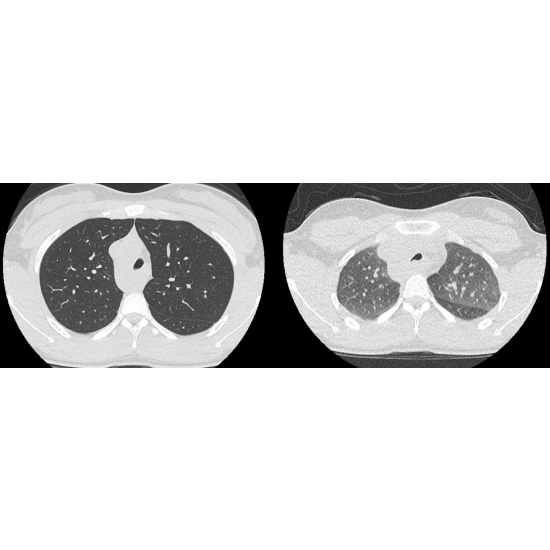

CT chest without contrast:

Right aortic arch with aberrant left subclavian artery arising from diverticulum of Kommerell, compatible with vascular ring Case Photo #4 .

Mild focal tracheal stenosis and tracheomalacia at the level of the vascular ring Case Photo #5 .